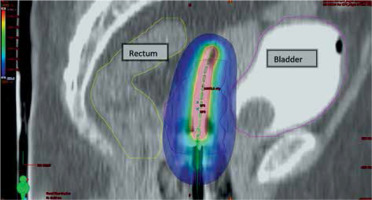

Fig. 4

Sagittal section of CT scan of ICBT application showing dose in color wash, blue shows prescribed dose 650 cGy